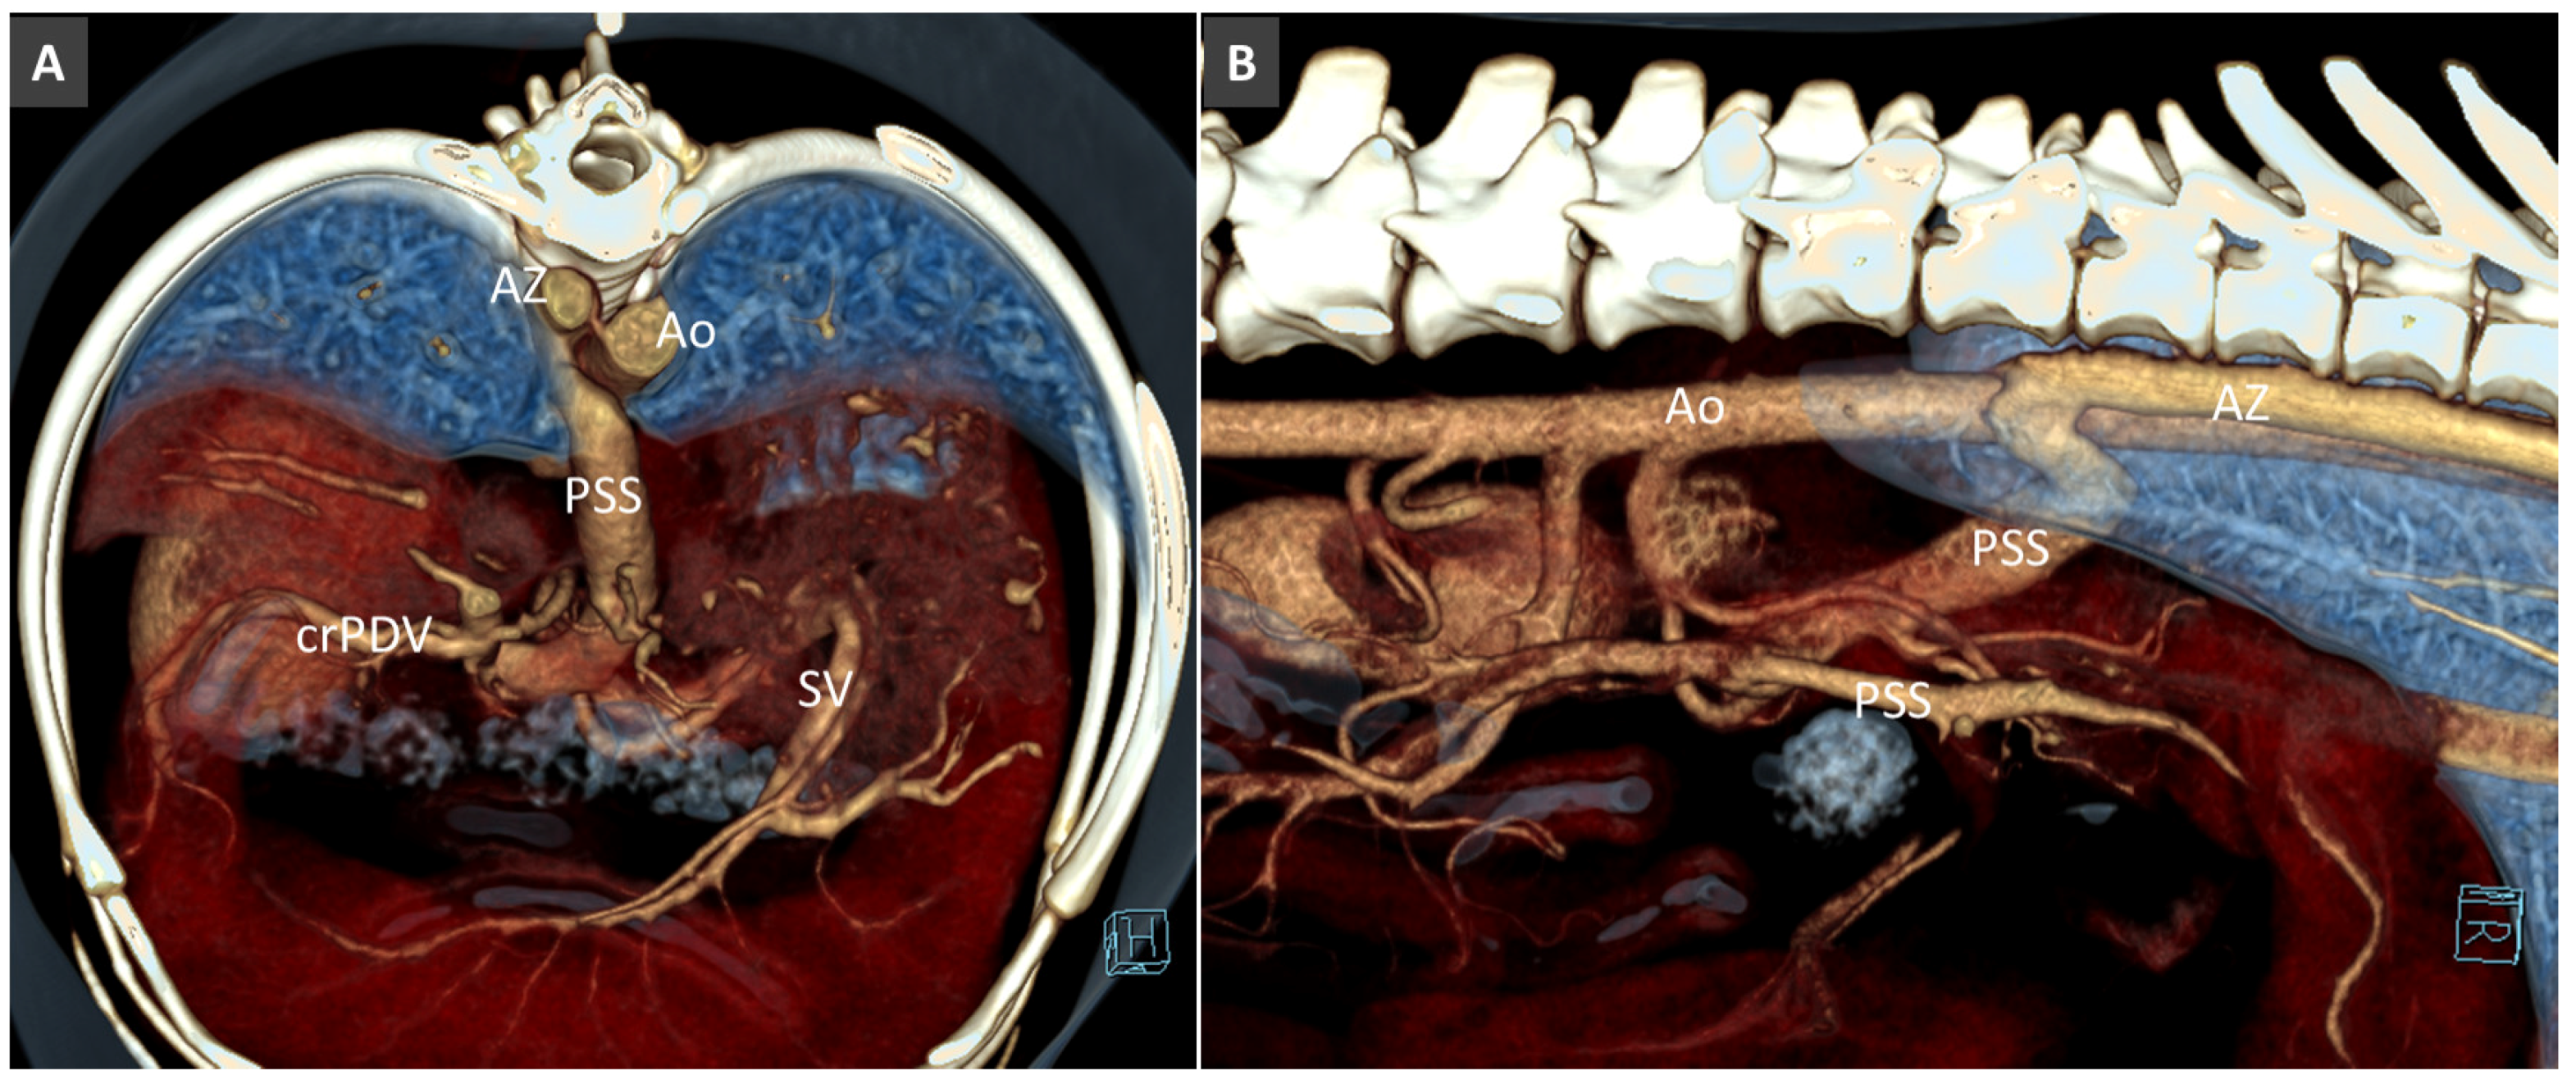

Congenital Portosystemic Shunt

3.8. Porto-Portal Collaterals or Cavernous Transformation of the Portal Vein